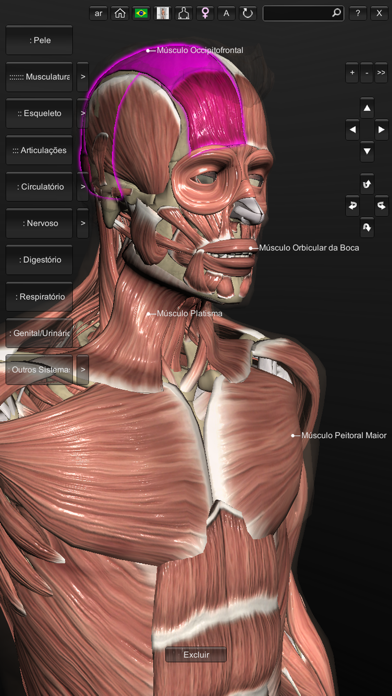

Explore a anatomia do corpo humano em todos os ângulos, de uma forma tridimensional e interativa. O aplicativo permite visualizar um modelo masculino* em 3D com todos os sistemas. (* o modelo feminino contido nesta versão inclui apenas o esqueleto e sistema reprodutor.) Em Português, Inglês, Espanhol e Latim (de acordo com a Terminologia Anatômica de 1998) - Novos comandos de toque: arraste 1 dedo para mostrar as legendas, 2 dedos para rotacionar o modelo, e 3 dedos para movê-lo -Agora com Realidade Aumentada (para IPhone6s ou superior) Este aplicativo foi projetado como um recurso adicional para o aprendizado de anatomia e não deve ser utilizado como fonte única de informação. Sistema incluídos: - esqueleto - musculatura contendo a origem e inserção - sistema nervoso - sistema circulatório (venoso e arterial) - sistema respiratório - ligamentos, cartilagens e articulações - sistema digestório - sistema urinário - sistema reprodutor - sistema linfático